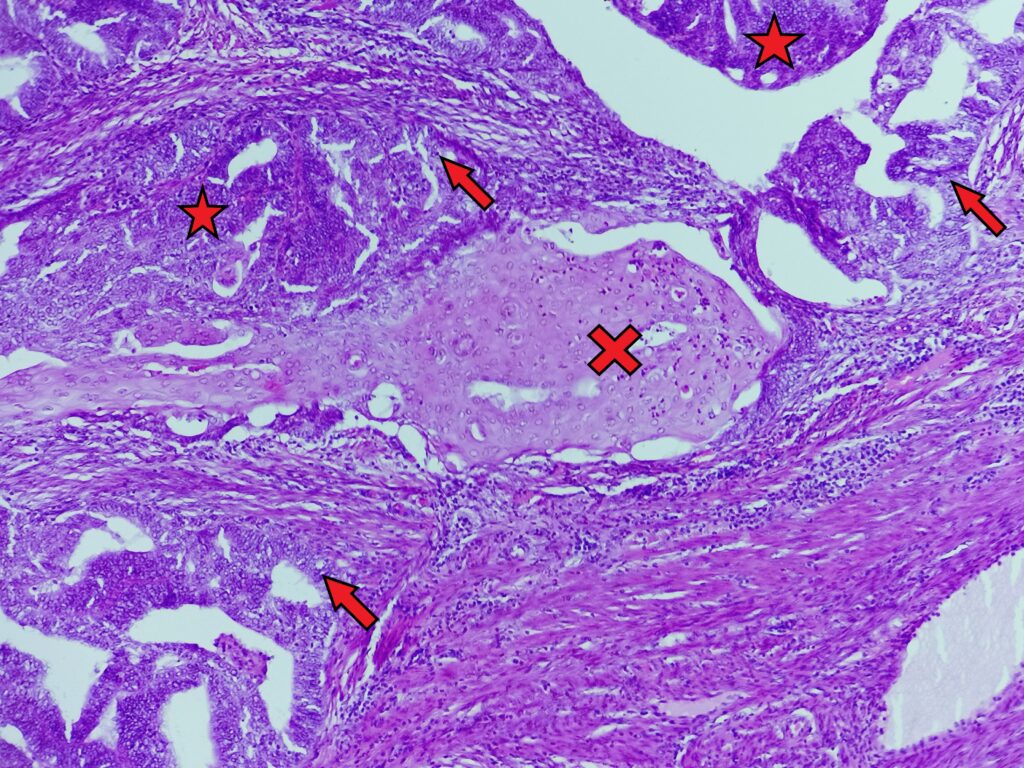

- w obrębie fragmentów błony śluzowej jamy macicy obecne są liczne, stykające się ze sobą nieprawidłowe gruczoły pozbawione oddzielającego podścieliska, o nieregularnym świetle, zajmujące więcej niż 2,1mm (połowa jednego pola widzenia o małym powiększeniu)

- gruczoły tworzące układy sitowate (gwiazdka), zrazikowe, brodawkowate i cewkowo- kosmkowe

- komórki zmiany wyraźnie różniące się od sąsiednich, niezmienionych – powiększone, walcowate (czerwona strzałka), jądra komórkowe powiększone, okrągłe, z utratą polarności, cytoplazma dość obfita, zwykle kwasochłonna i ziarnista, jąderka zwykle nie są bardzo wyraźne

- obecność ogniskowego różnicowania płaskonabłonkowego lub morul płaskonabłonkowych (krzyżyk) – owalne lub okrągłe lub nieregularne struktury składające się z komórek o wyraźnej, obfitej, kwasochłonnej cytoplazmie

- brak komponenty sarkomatycznej, dominującego tworzenia układów brodawkowatych, dominujących komórek z atypią dużego stopnia i licznymi figurami podziału, dominujących komórek hufnalowych o jasnej cytoplazmie

Rak gruczołowy endometrioidny trzonu macicy (Endometrial endometrioid adenocarcinoma of the uterine corpus).